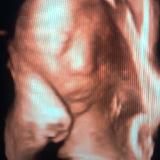

UZI KIM ANNA

Клиника "Central med" Режим работы: с 8:00 до 15:00 каждый день кроме воскресенья Адрес клиники: Ц6 ул Ш. Рашидова 94а. Ориентир напротив Пожарки. По вопросам пишите в личку @annakimrom Тел: 90 1871060 99 8647444